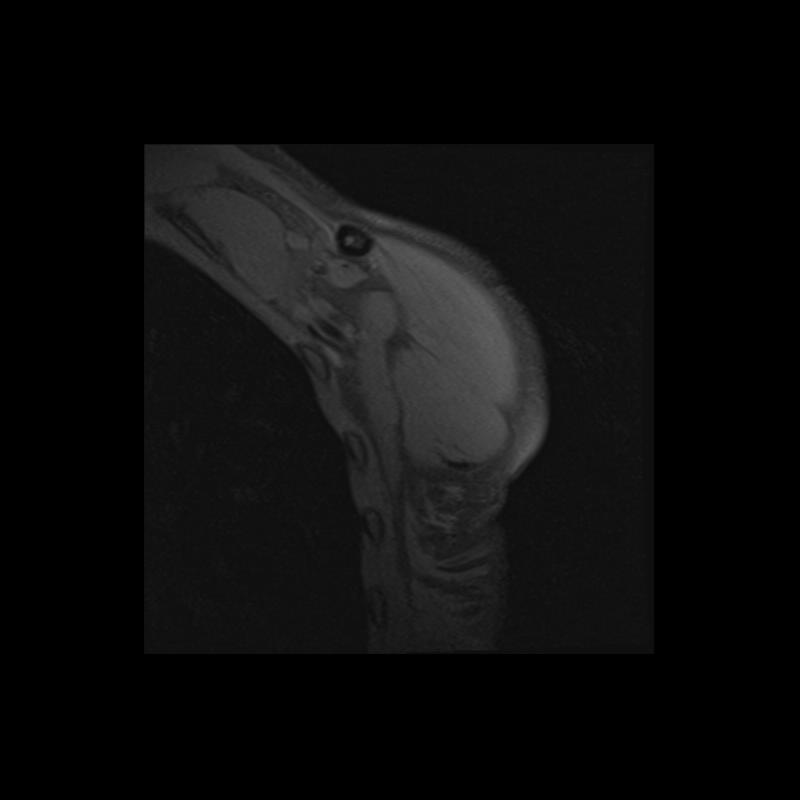

Shoulder MRI Anatomy